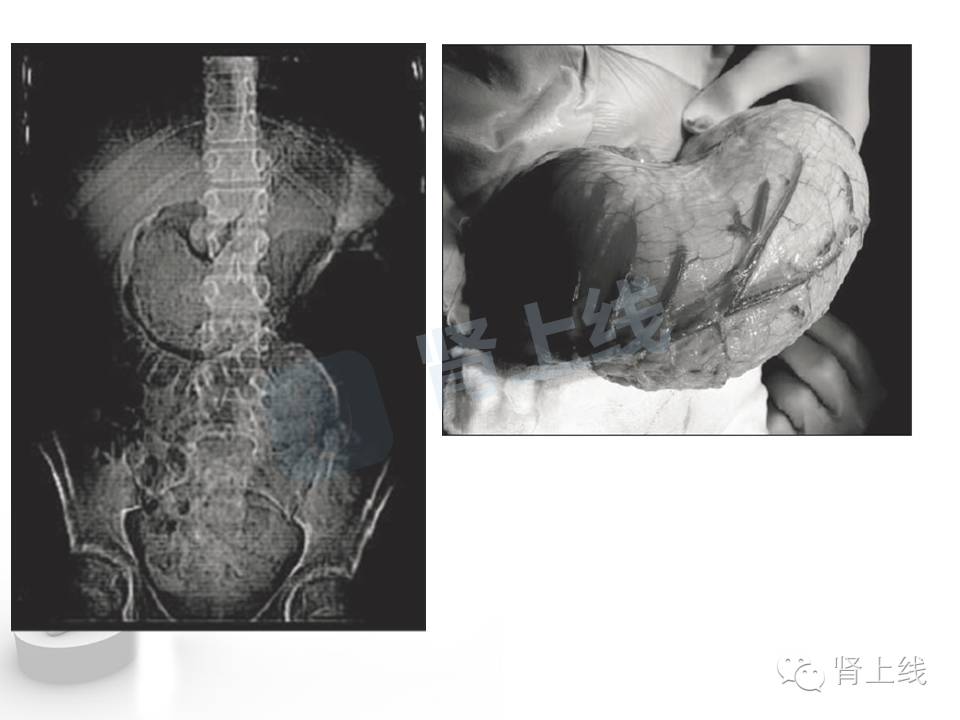

手术中可以看到被头发撑得巨大的胃,这到底吃了多少?

好吧,惊魂未定后,我们再来看看毛发性胃结石,恩,没错,顾名思义,就是吃了太多头发,胃消化不了,排不出去,形成的结石。